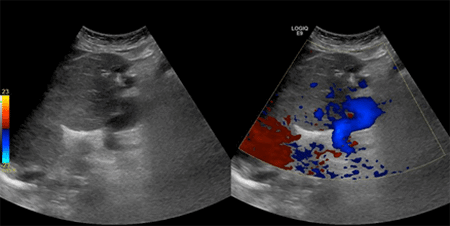

A large dilated left gastric vein was noted. Additionally, periesophageal, perigastric, perisplenic, and mesenteric varices were present with moderate ascites and splenomegaly. Due to the PVT extending to the confluence of superior mesenteric vein (SMV), an abdominal ultrasound was performed to evaluate the left gastric vein flow for possible left gastric-portal anastomosis. Ultrasound showed a patent left gastric vein dilated to 2 cm in the mid-epigastrium with phasic variations (Figure 3) with an average velocity of 42.1 cm/sec. Given the sufficient size and flow of the patient’s left gastric vein, a surgical plan for gastric-portal anastomosis for liver allograft inflow was pursued.

Figure 3. Preoperative Ultrasound Demonstrating Sufficient Size and Inflow of Left Gastric Vein. Published with Permission